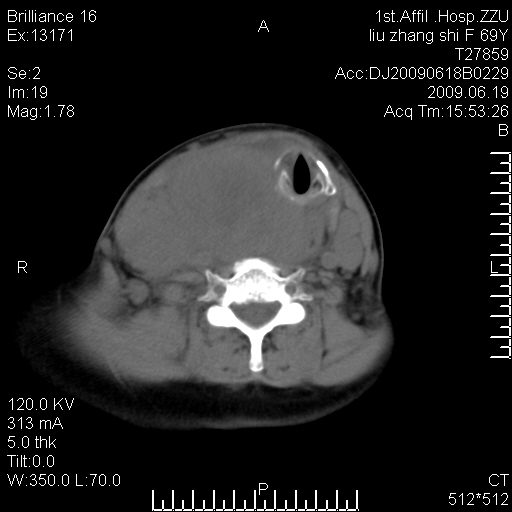

标题: CT26782:女,69岁,颈部占位,3天后公布病理结果。

【病理证实系列】女,69岁,颈部占位,有病理结果,3天后公布。(由于病例时间较久,临床资料不全,请网友见谅)本系列将有几百种常见、少见及罕见病例,均经病理证实。病例资料来自郑州大学第一附属医院。与网友共享,本人有空就发。

甲状腺癌并颈部淋巴结转移。感谢楼主的良苦用心,谢谢。

甲状腺癌并颈部淋巴结转移。

需与鼻咽癌鉴别!

支持甲状腺癌广泛侵及周围结构并颈部淋巴结转移。

鉴别:淋巴瘤、恶性神经源性病变、恶性纤维组织细胞瘤。

病理结果:颈部非霍奇金淋巴瘤。

右侧甲状腺确实有问题